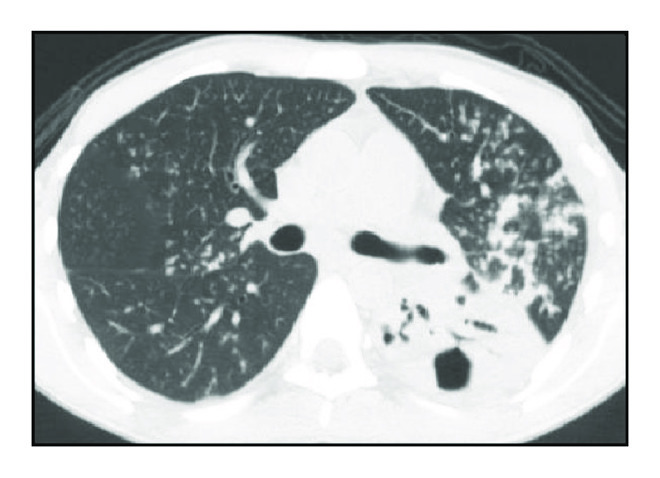

Regarding severity of the disease, multiple bilateral involvement was observed in 52 patients (70.3%) (Table 1 and Figure 1).

(a)

(b)

(c)

(d)

Tree-in-bud pattern was observed in 69 cases (93%) and was always associated with other types of injury, including consolidation in 57 cases (77%) and cavitary lesions in 46 cases (62%). Consolidations predominated in the upper lobes and occurred on the left lobe in 32 cases (56%) and on the right lobe in 22 cases (38%). Cavitary lesions predominated in upper lobes and occurred in upper left lobe in 22 cases (47.8%) and in upper right lobe in 15 cases (32.0%). The left and right lungs were affected separately in 12 cases (16.2%) and 10 cases (13.5%), respectively. Involvement of a single lobe was observed in 21% of cases, two lobes were involved in 21% of cases, three lobes in 19% of cases, and more than three lobes in 37% of cases. The upper lobe was affected in 72% of cases, the lingular and middle lobes were affected in 36% and 33% of cases, respectively, the right lower lobe was affected in 40% of cases, and the left lower lobe was affected in 60% of cases. Analysis by segment indicated that the most affected segments were the apical and posterior segments of the upper lobes in 63% and 66% of cases, respectively, and the apical segments of the lower lobes (41% of cases involving the right lobe and 52% of cases involving the left lobe).